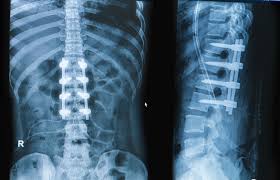

Spine surgery helps treat conditions that cause persistent pain, weakness, or restricted movement. These conditions include disc problems, spinal stenosis, degenerative spine changes, and nerve compression. Therefore, spine surgery directly addresses the root cause rather than only managing symptoms.

Modern spine surgery focuses on precision and minimal disruption to surrounding tissues. Therefore, surgeons use advanced techniques that support faster healing and reduced post-surgical discomfort. These techniques aim to stabilize the spine while protecting nerves and muscles.

Moreover, customized surgical planning allows better alignment and correction. As a result, patients experience improved posture, reduced pain, and enhanced movement after surgery.